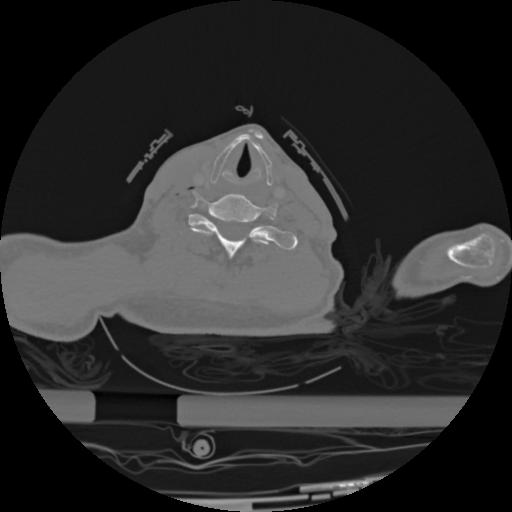

22 ANGIO,CE,Vol,0.5,ANGIO,,